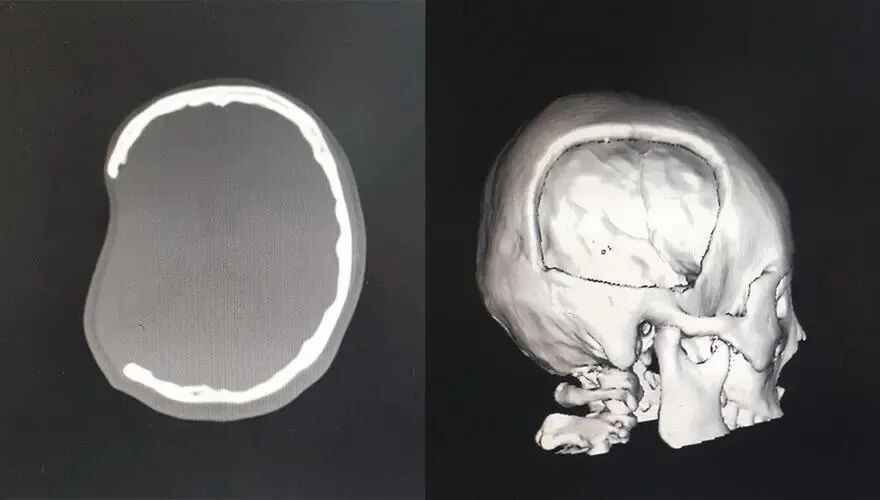

颅骨缺损大部分患者是因为开放性颅脑损伤或者火器伤所引起的,有一部分创伤患者是由于粉碎性的骨折因手术去除不能完全复位,或者清除颅内血肿后去除骨瓣,而引起的颅骨缺损。也会有一部分患者,是由于肿瘤侵袭颅骨,或者为脑减压而去除颅骨瓣,从而引起颅骨缺损的。

目前传统认为颅骨修补术在去骨瓣减压术后3-6个月进行,但是新的权威临床研究认为,患者在去骨瓣减压术后,由于颅骨缺损,脑血管功能代偿受到影响,脑脊液及颅内压调节紊乱,严重影响脑组织新陈代谢,不利于脑组织的再生、修复、和功能代偿。随着时间延长,诱发脑细胞水肿、细胞凋亡、氧化应激等,从而引起神经元损伤、神经功能障碍。研究表明,颅骨缺损时间越长,患者神经功能越差。《创伤性颅骨缺损成形术中国专家共识(2016)》专家推荐意见:如无手术禁忌证,在病情允许的情况下,提倡早期行颅骨成形术。即颅内压趋于稳定,颅骨缺损处由膨起变平或凹陷时就做修补,当然,这个是根据患者颅骨缺损处的情况来定的,一般都能在两个月内,有的甚至在一个月左右。

颅骨缺损严重影响脑功能及意识恢复,颅骨缺损为患者早期康复治疗带来障碍及相应并发症!颅骨缺损的时间愈长,颅骨缺损综合征及继发性脑损害的发生率愈高。为了恢复颅腔的固定的密闭性,保持生理性颅内压稳定,减轻颅骨缺损综合征。对颅骨缺损直径在3厘米以上,无肌肉覆盖,无禁忌证者都应行早期颅骨修补。解决缺损区没有对脑组织的有效保护、供血障碍、脑脊液循环异常等问题,还需要解决外形修复整形的问题等。所以,颅骨缺损后应当及时早期行颅骨修补术。